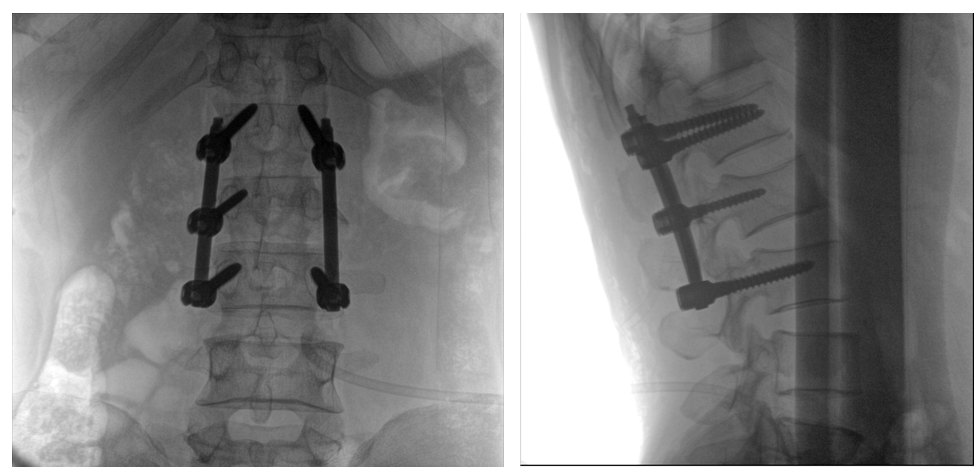

病例一:

患者不慎摔傷,傷后腰部疼痛,腰2椎體壓縮性骨折,遂以“椎弓根釘內(nèi)固定術(shù)”治療。椎弓根螺釘可以從椎體后方貫穿到椎體前方,達(dá)到椎體三柱固定,但是手術(shù)過程中要保對多節(jié)錐體進(jìn)行手術(shù),所以要求圖像要盡可能的展現(xiàn)出全節(jié)段腰椎。

一體式C形臂全節(jié)段腰椎臨床影像

普愛醫(yī)療PLX119C大平板一體式C形臂采用30CM×30CM的平板探測器,一般可一次性成像5節(jié)腰椎,呈現(xiàn)更廣闊的視野。使醫(yī)生一次性全面地觀察到傷椎及周圍椎體情況,使得手術(shù)效率更高、更準(zhǔn)確。